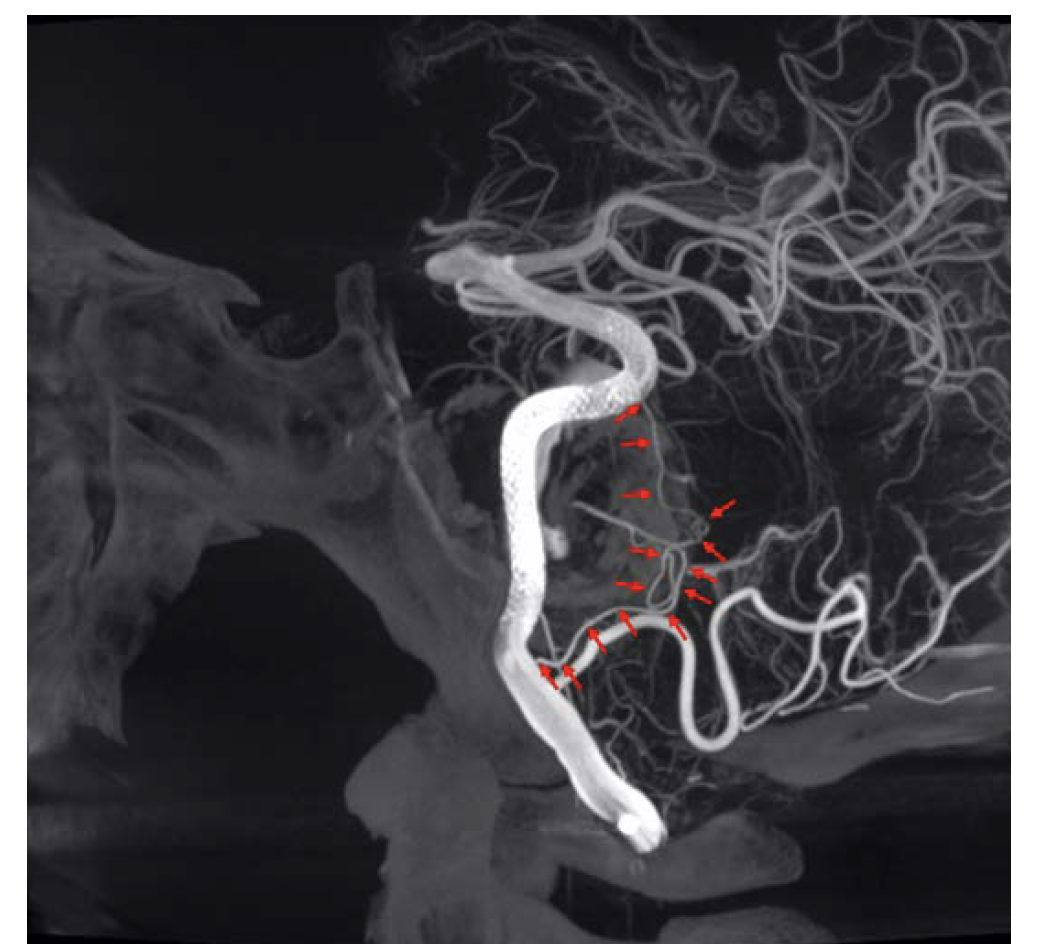

After a 3-stent construct was built, a DynaCT Micro with contrast was obtained, which demonstrated excellent stent-stent and stent-wall apposition (Figure 15). Even more important, it resolved an entire collateral arcade, replacing the native basilar artery and extending from the distal left vertebral artery (no stent covering the origin) to the distal basilar artery (1-stent coverage). This anatomic resolution enabled a more aggressive approach to the aneurysm neck, and ultimately 6 stents were placed. This anatomic collateral has previously been theorized and assumed to occur in the setting of giant midbasilar aneurysms without infarct. However, with DynaCT Micro, it can actually be visualized.

The original plan was to coil off the right vertebral artery distal to PICA. However, the imaging resolution of the ARTIS icono enabled visualization of critical medullary perforators distal to the PICA origin (Figure 16). The plan was therefore modified to coil off the vertebral distal to the most distal of these perforators. The distal right vertebral artery was successfully embolized distal to the perforators (Figure 17).